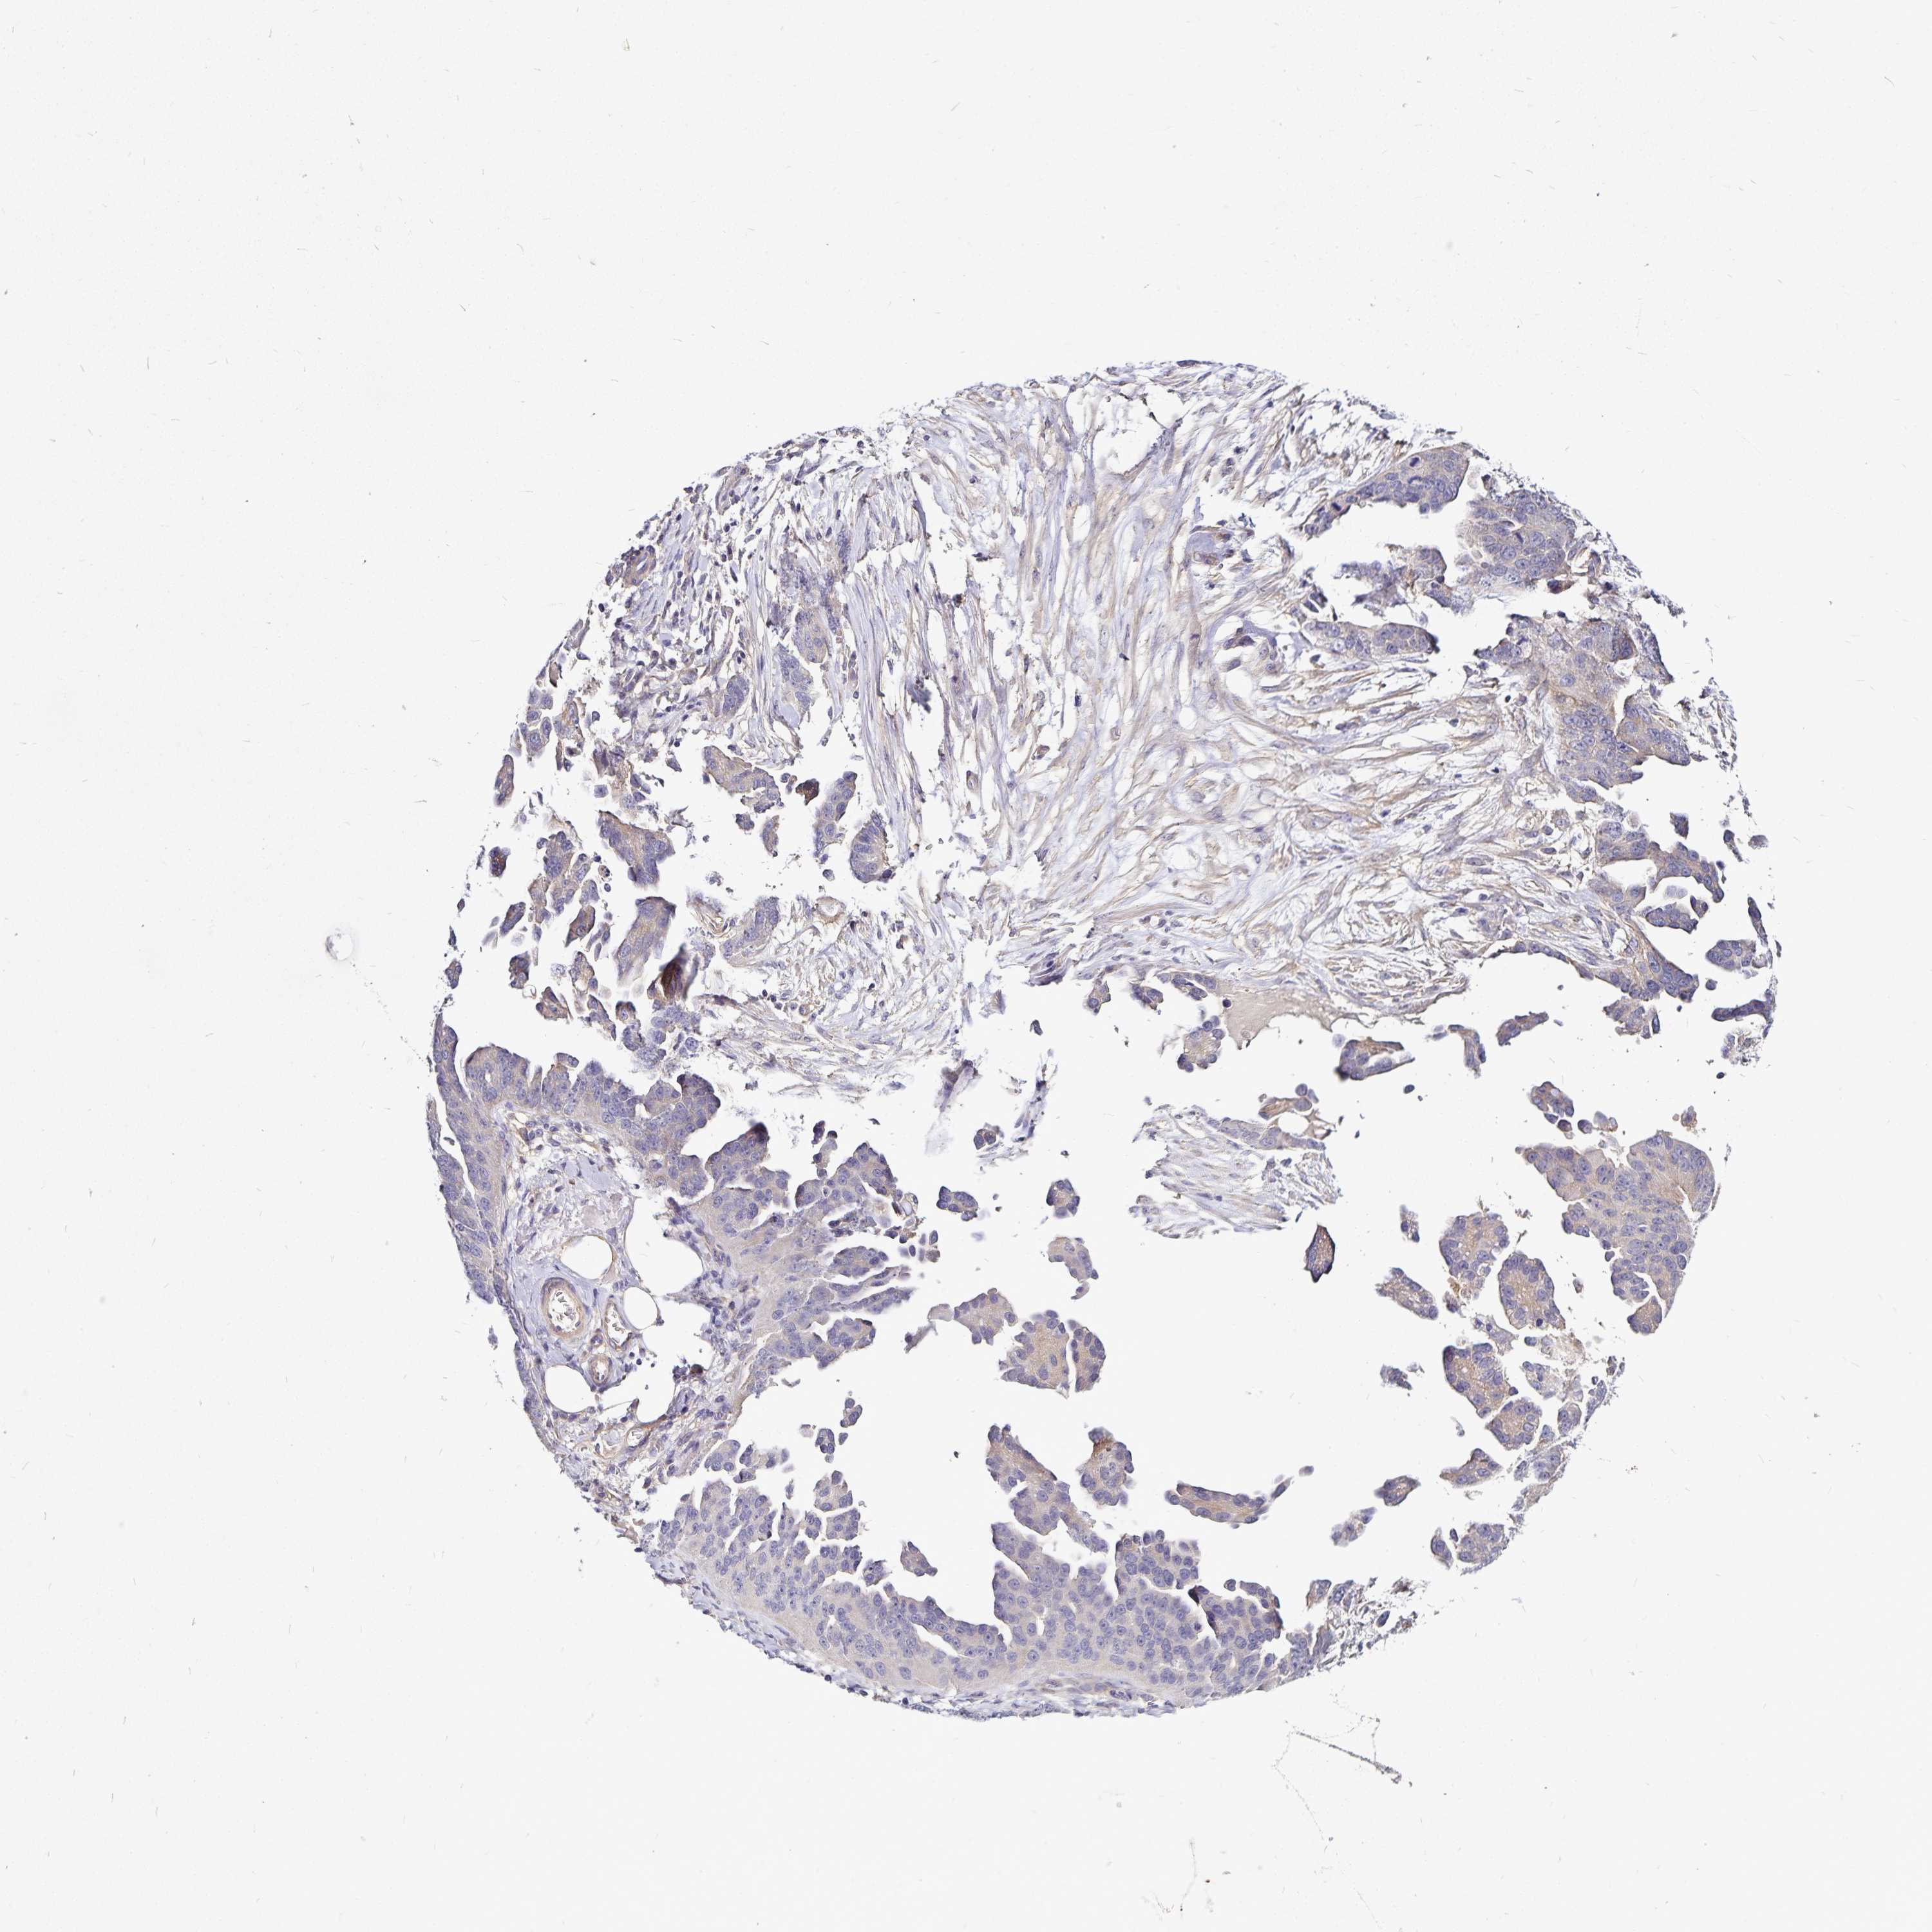

OVARIAN CANCER - Protein expressioni

A mouse-over function shows sample information and annotation data. Click on an image to view it in a full screen mode. Samples can be filtered based on level of antibody staining by selecting one or several of the following categories: high, medium, low and not detected. The assay and annotation is described here.

Note that samples used for immunohistochemistry by the Human Protein Atlas do not correspond to samples in the TCGA dataset.

Antibody stainingi

Antibody staining in the annotated cell types in the current human tissue is reported as not detected, low, medium, or high, based on conventional immunohistochemistry profiling in selected tissues. This score is based on the combination of the staining intensity and fraction of stained cells.

Each image is clickable and will lead to virtual microscopy that enables deeper exploration of all samples and also displays staining intensity scores, fraction scores and subcellular localization as well as patient and tissue information for each sample.

Antibody HPA057790

Antibody HPA062208

Staining

High

Medium

Low

Not detected

Intensity

Strong

Moderate

Weak

Negative

Quantity

>75%

75%-25%

<25%

None

Location

Nuclear

Cytoplasmic/membranous

Cytoplasmic/membranous,nuclear

Cystadenocarcinoma, serous, NOS

Cystadenocarcinoma, mucinous, NOS

Carcinoma, endometroid